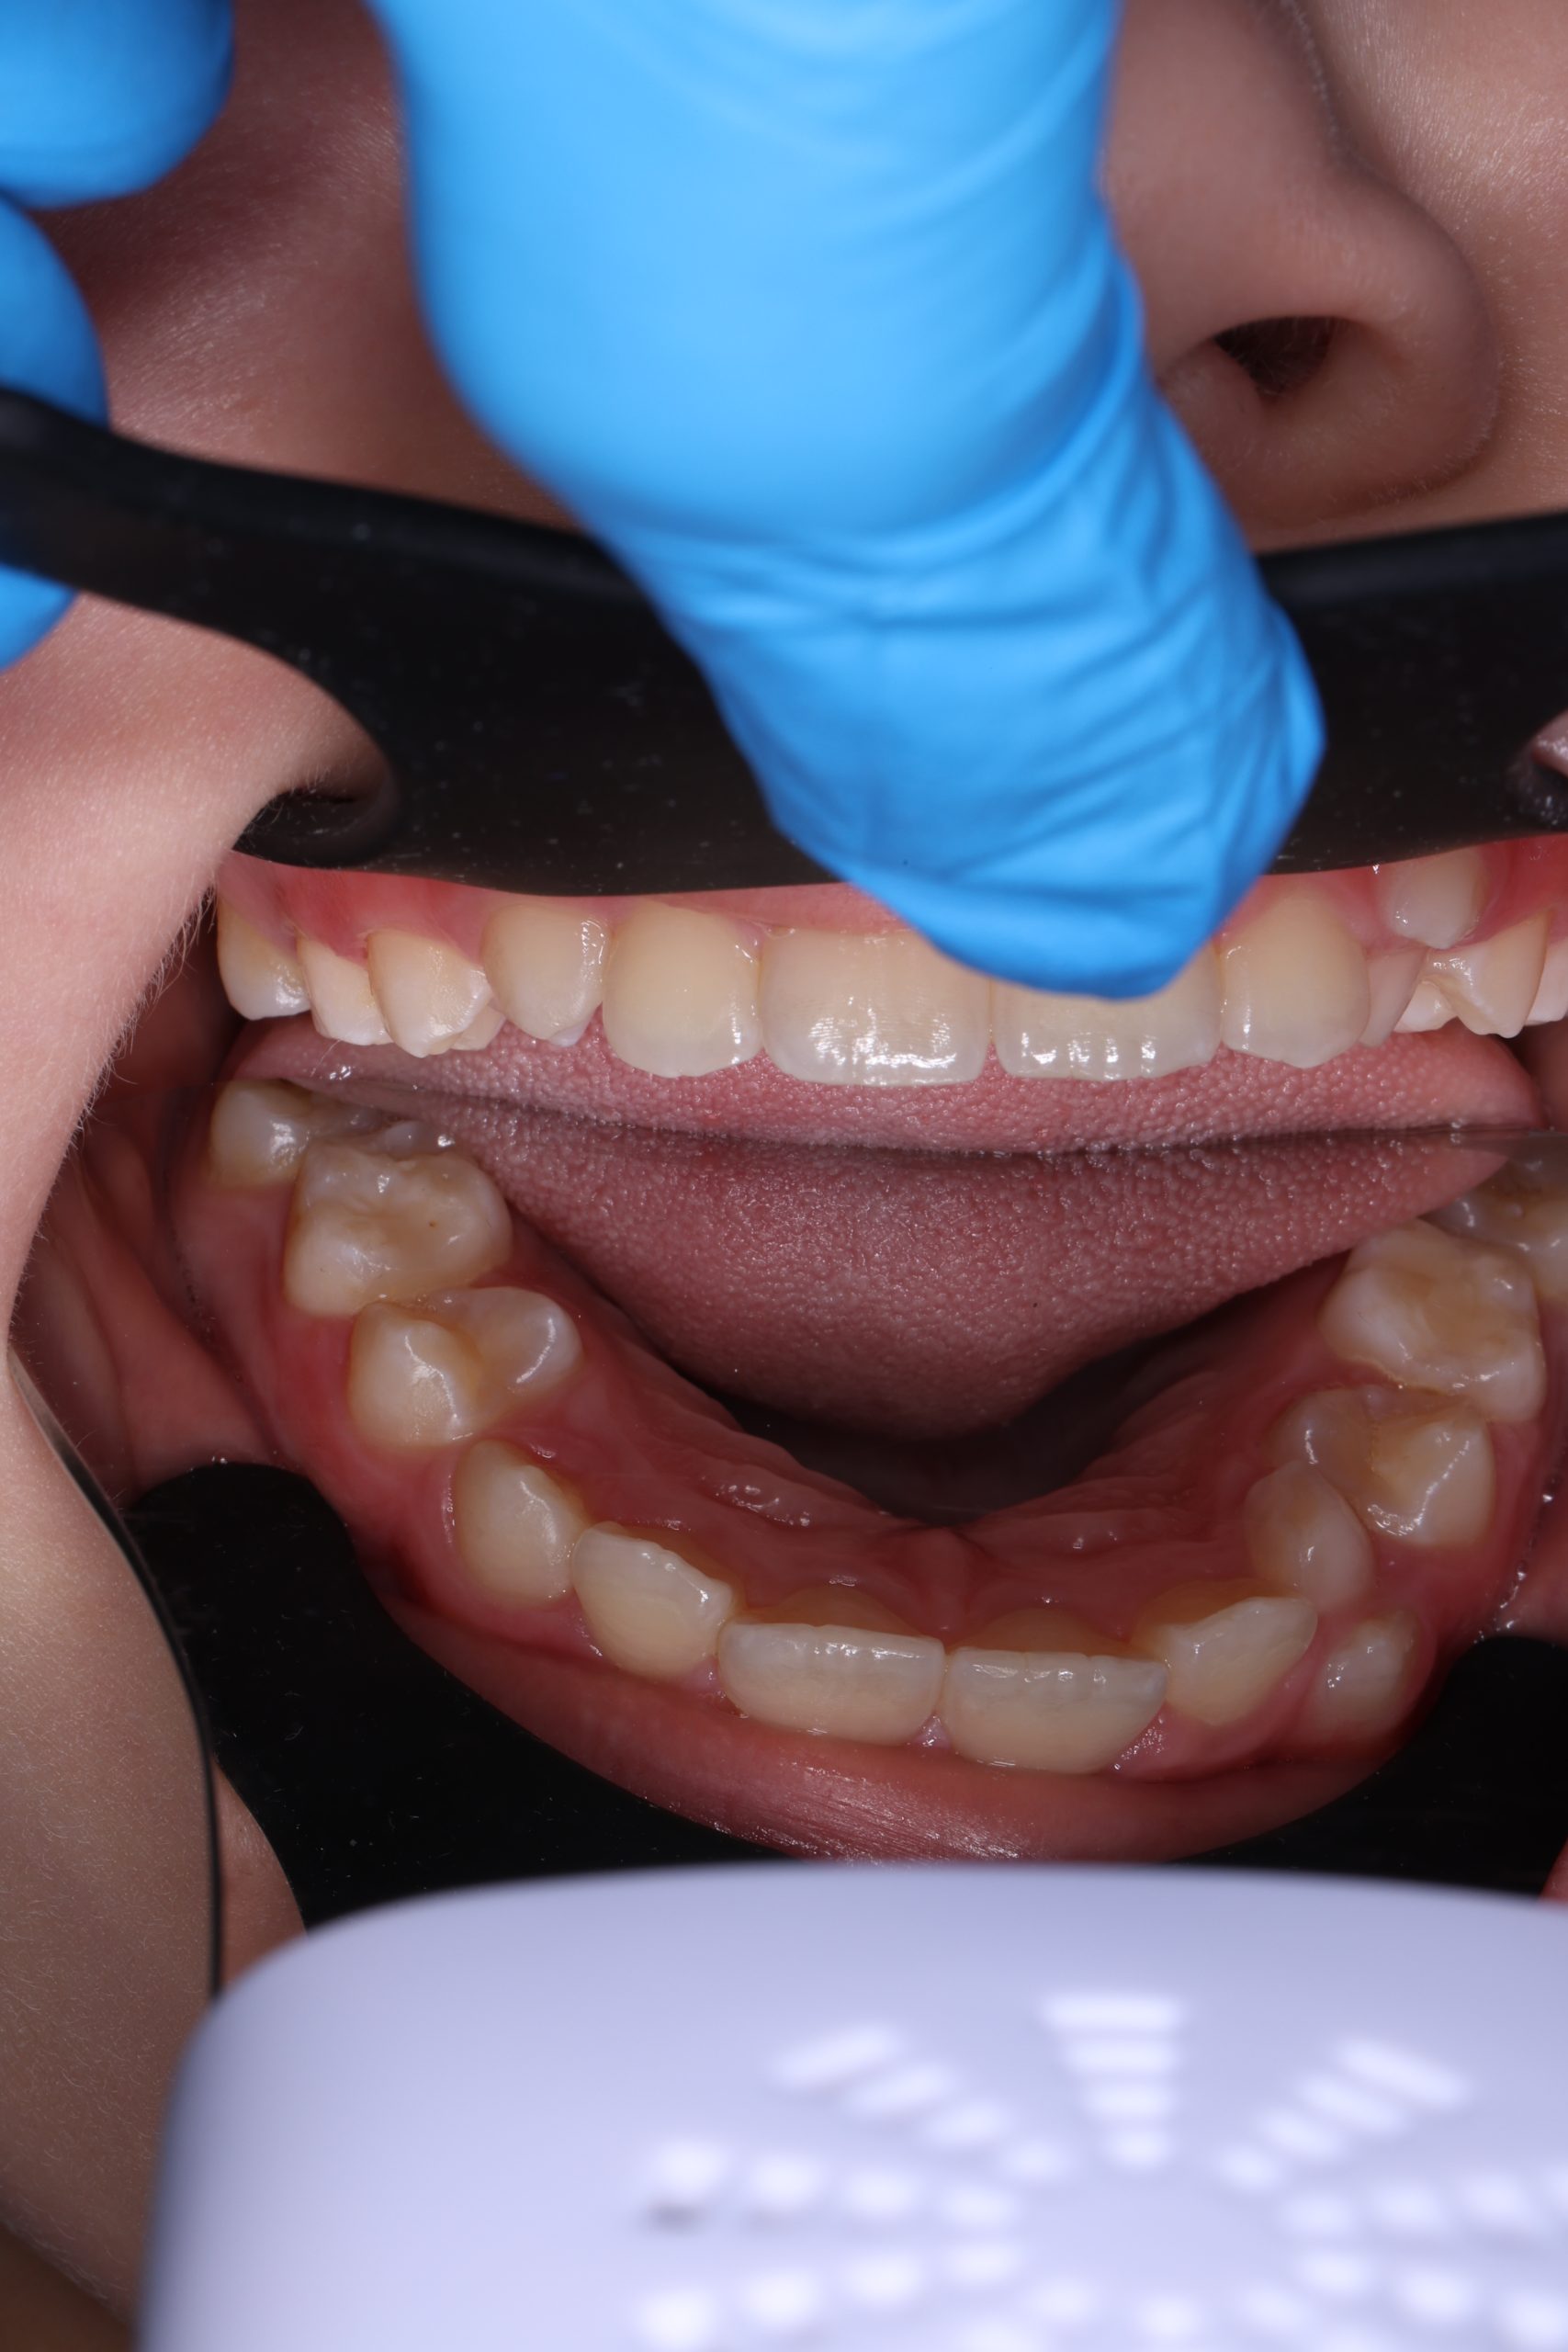

We examine the condition of teeth, gums, and bite. - Plaque Disclosure with Special Indicators

Areas that weren’t cleaned well appear purple. The darker the shade, the older the plaque. This helps both kids and parents understand where brushing needs to improve. - Brushing Training & Home Care Tools Selection